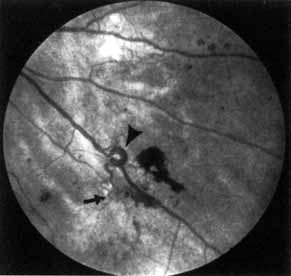

Fig. 8 Venous loop (large arrow) and intraretinal microvascular abnormalities (IRMA; small arrow).

Venous beading (see Fig. 7) and venous loops (see Fig. 8) indicates sluggish retinal circulation and are nearly always adjacent to extensive areas of capillary nonperfusion. Focal vitreous traction is thought to contribute to their formation.9 Capillaries next to areas of nonperfusion that dilate and function as collaterals are referred to as IRMA. They are frequently difficult to differentiate from surface retinal neovascularization. Fluorescein, however, does not leak from IRMA but leaks profusely from neovascularization (see Fig. 7).